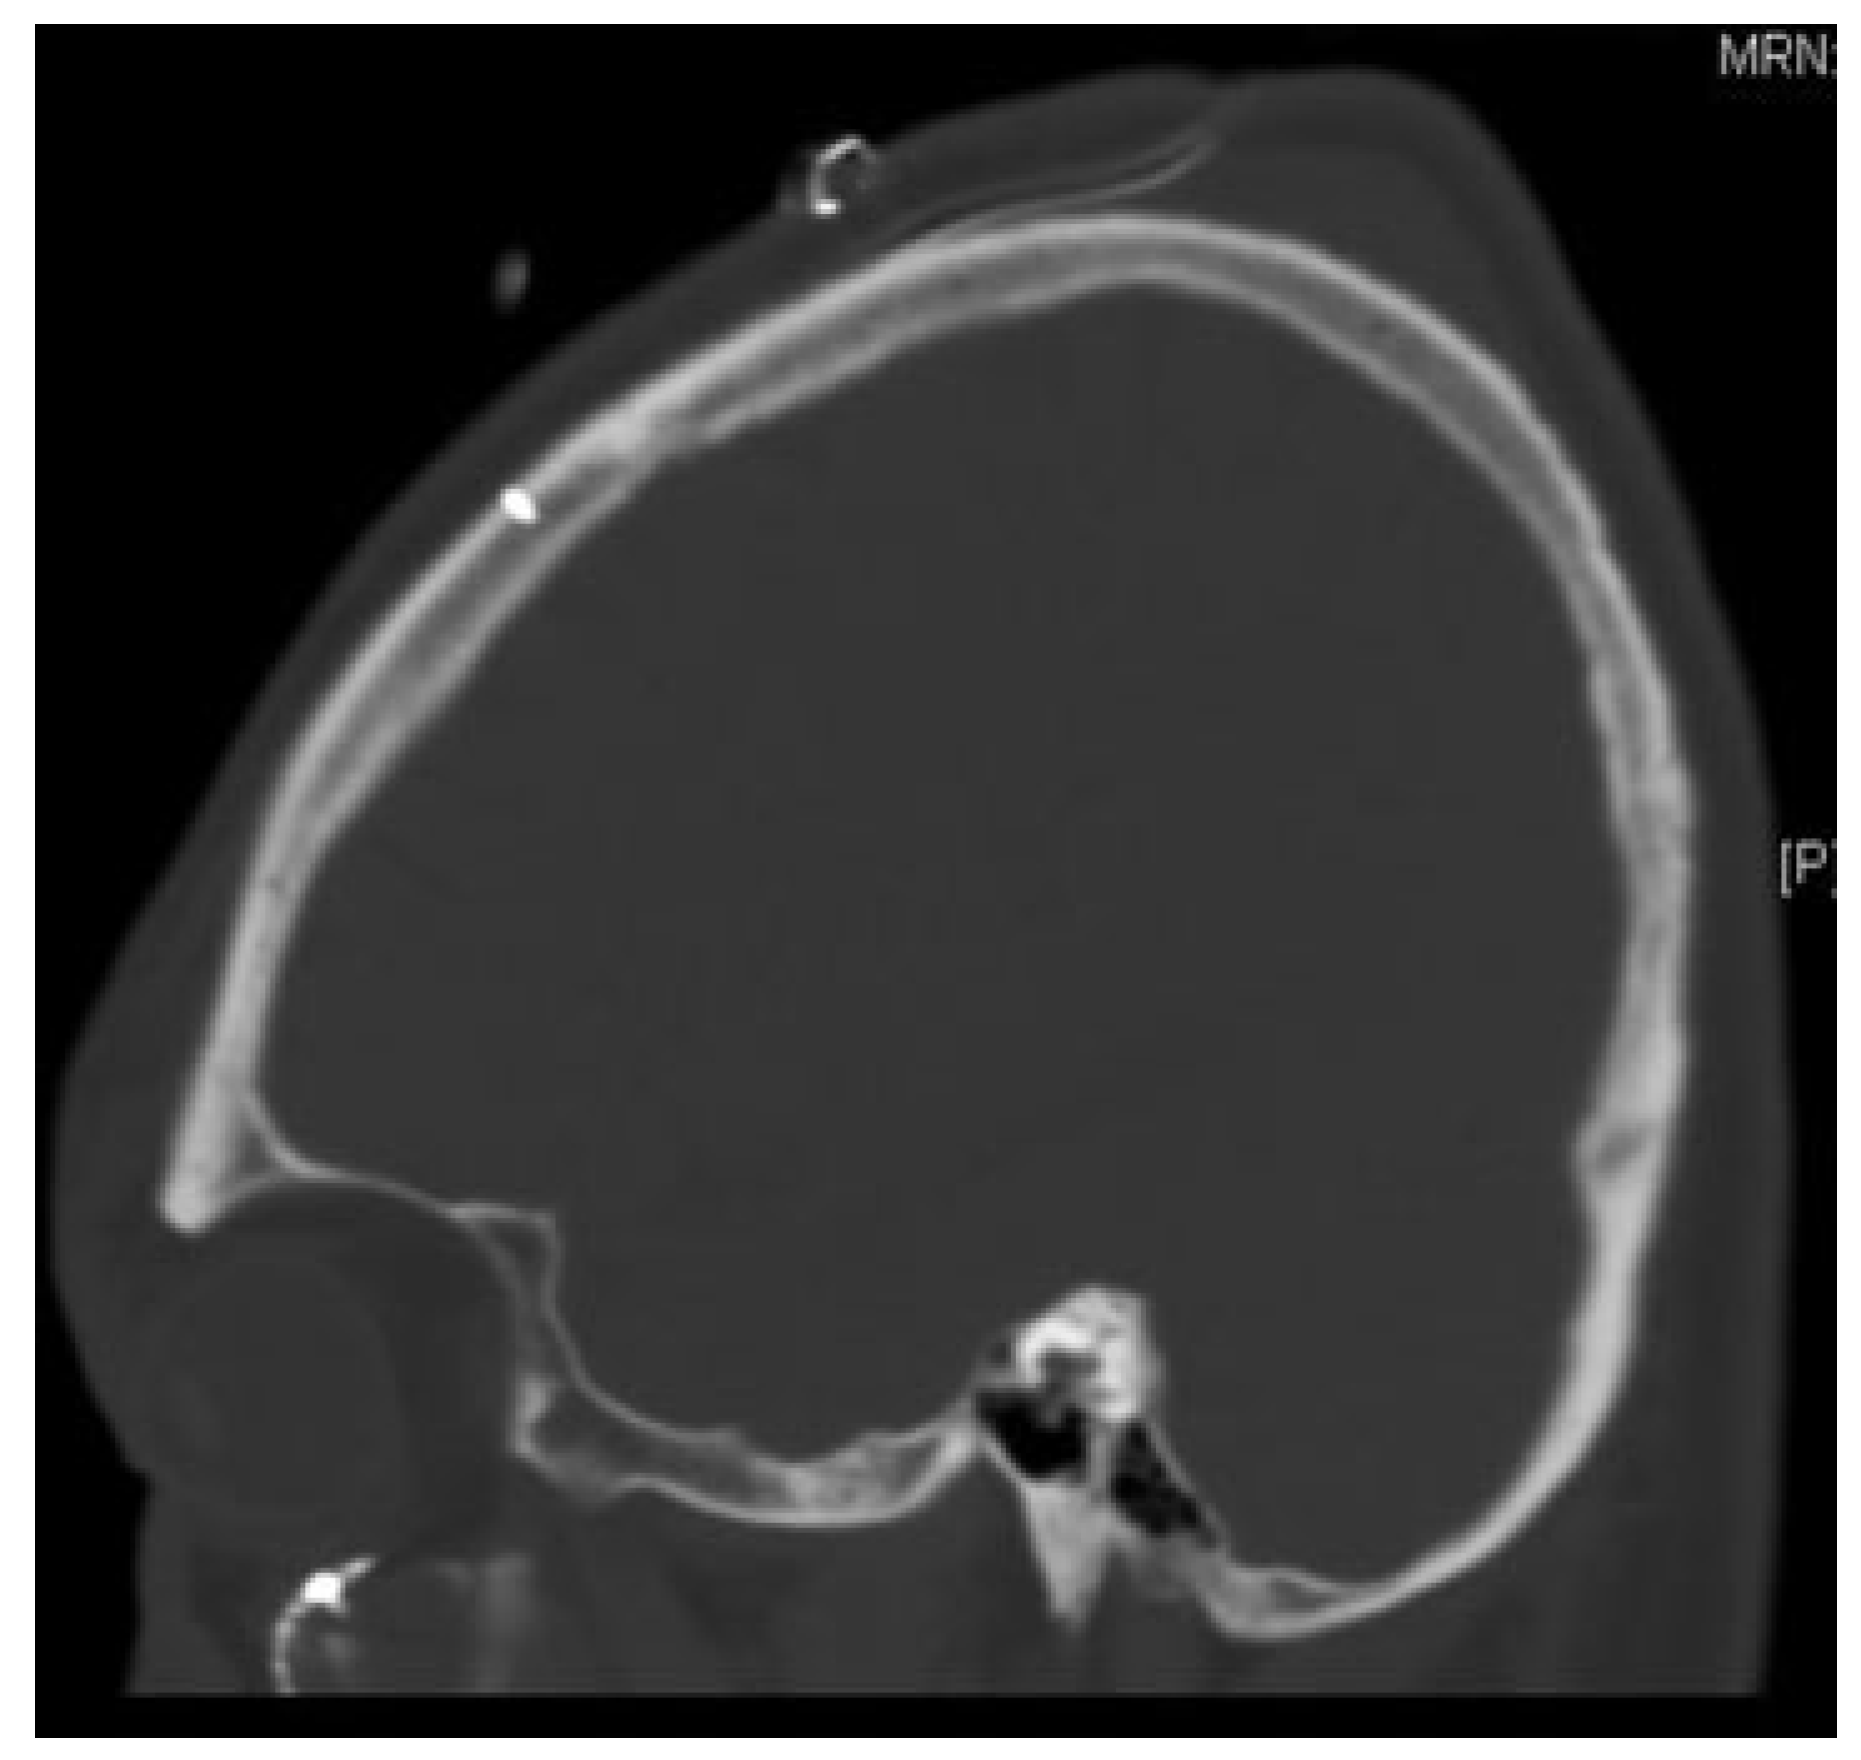

| Patient | Age/sex | Other injuries | Operative changes | Fractured implant | Point of fracture |

|---|---|---|---|---|---|

| 1 | 42 M | NIL | NIL | Screw 1.5 mm | Neck of screw |

| 2 | 25 M | Subdural hemorrhage, cervical spine spinal process fractures, left scapula fracture, rib fractures | Plate moved slightly medial | Drill bit 1.1 mm | Shaft |

| 3 | 28 M | Rib fractures, sternal fracture, multiple vertebral body, and spinal process fractures | NIL Titanium mesh—different hole used | Drill bit 1.1 mm | Shaft |

| 4 | 58 M | Left femur fracture, left radius ulnar fracture, intracerebral hemorrhage | NIL Titanium mesh—different hole used | Drill bit 1.1 mm | Shaft |

| 5 | 32 M | Right femoral fracture | NIL Titanium mesh—different hole used | Drill bit 1.1 mm | Shaft |